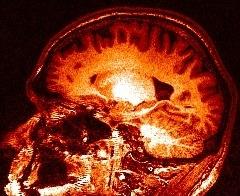

You may think that a unequivocal correspondence exists between the grey level in one voxel of a T1-weighted MR scan, and some esoteric property of the underlying cube of tissue. You should not succumb to this temptation. Take some time to observe a standard anatomical scan with a rainbow colormap to have this revelation:

Some parts of the white matter are red, while some others are yellow or even green. All looks like as if the putative correspondence mentioned above was depending on the localization in the field of view. Usually, the center of the coil is lighter, but this is not a systematic observation and depends on the coil and scanner design. When one looks at a MR slice with a grey colormap, like in standard radiology, this default is not straightforward. Human vision, indeed, is very effective at correcting for this kind of spatial variations. This capacity has some link with the fact that we usually perceive object's colors as uniform, whatever illumination related variations. Unfortunately, this sophisticated feature of human vision has prevented the MR physicists to find the motivation to overcome that acquisition problem. Artificial vision still being in its infancy, it is much more disturbed by these spatial intensity variations than radiologists. This procedure has to correct for the spatial bias before any segmentation process can be reliably trigered.